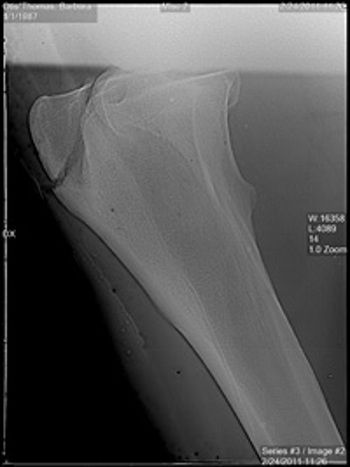

Our digital radiograph unit allows us to instantly see a high-quality image patient-side. This image can be adjusted to pick up even the most minor orthopedic changes. Images are stored electronically and copies on CD are available to you as well.

xray fracture